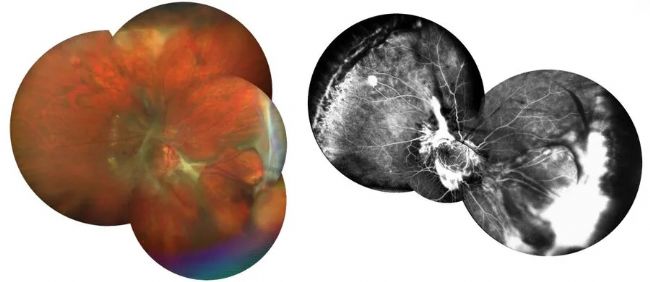

一名患有馮-希佩爾-林道(VHL)綜合征的 30 歲女性失去了左眼,右眼視力仍相對較好,但視力正在下降。她的左眼失明,右眼視力仍相對較好,但視力卻在下降。她的右眼有大量眼膜需要切除,還有幾個血管母細(xì)胞瘤,其中一個非常大(圖 9)。

圖 9:術(shù)前圖像。患者有多個血管母細(xì)胞瘤,其中一個非常大。圖片由 Nikolaos Bechrakis 教授提供。

術(shù)中 OCT 顯示視網(wǎng)膜脫落,而且術(shù)前沒有看到的是視網(wǎng)膜下膜和視網(wǎng)膜下間隙的血管瘤(圖 10)。這對了解具體情況以及牽引性視網(wǎng)膜脫離是如何形成的非常有用。通過評估,外科醫(yī)生得出結(jié)論,牽引性視網(wǎng)膜脫離不僅是由視網(wǎng)膜外膜造成的,也是由視網(wǎng)膜下膜造成的。

圖 10:術(shù)中 OCT 圖像顯示,視網(wǎng)膜下有一層膜,視網(wǎng)膜下間隙有一個血管瘤。圖片由 Nikolaos Bechrakis 教授提供。